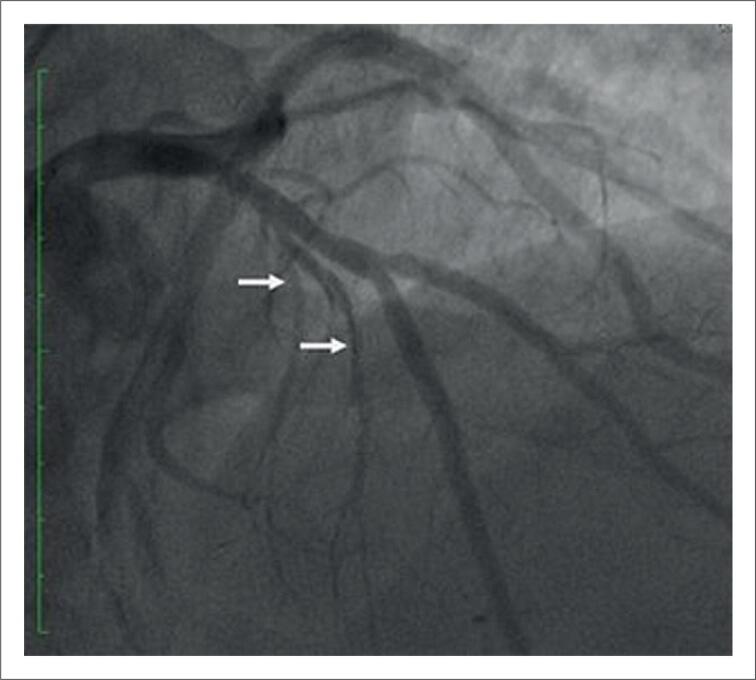

Septal Artery Embolization with Onyx® In Hypertrophic Cardiomyopathy: Report of Two Cases.